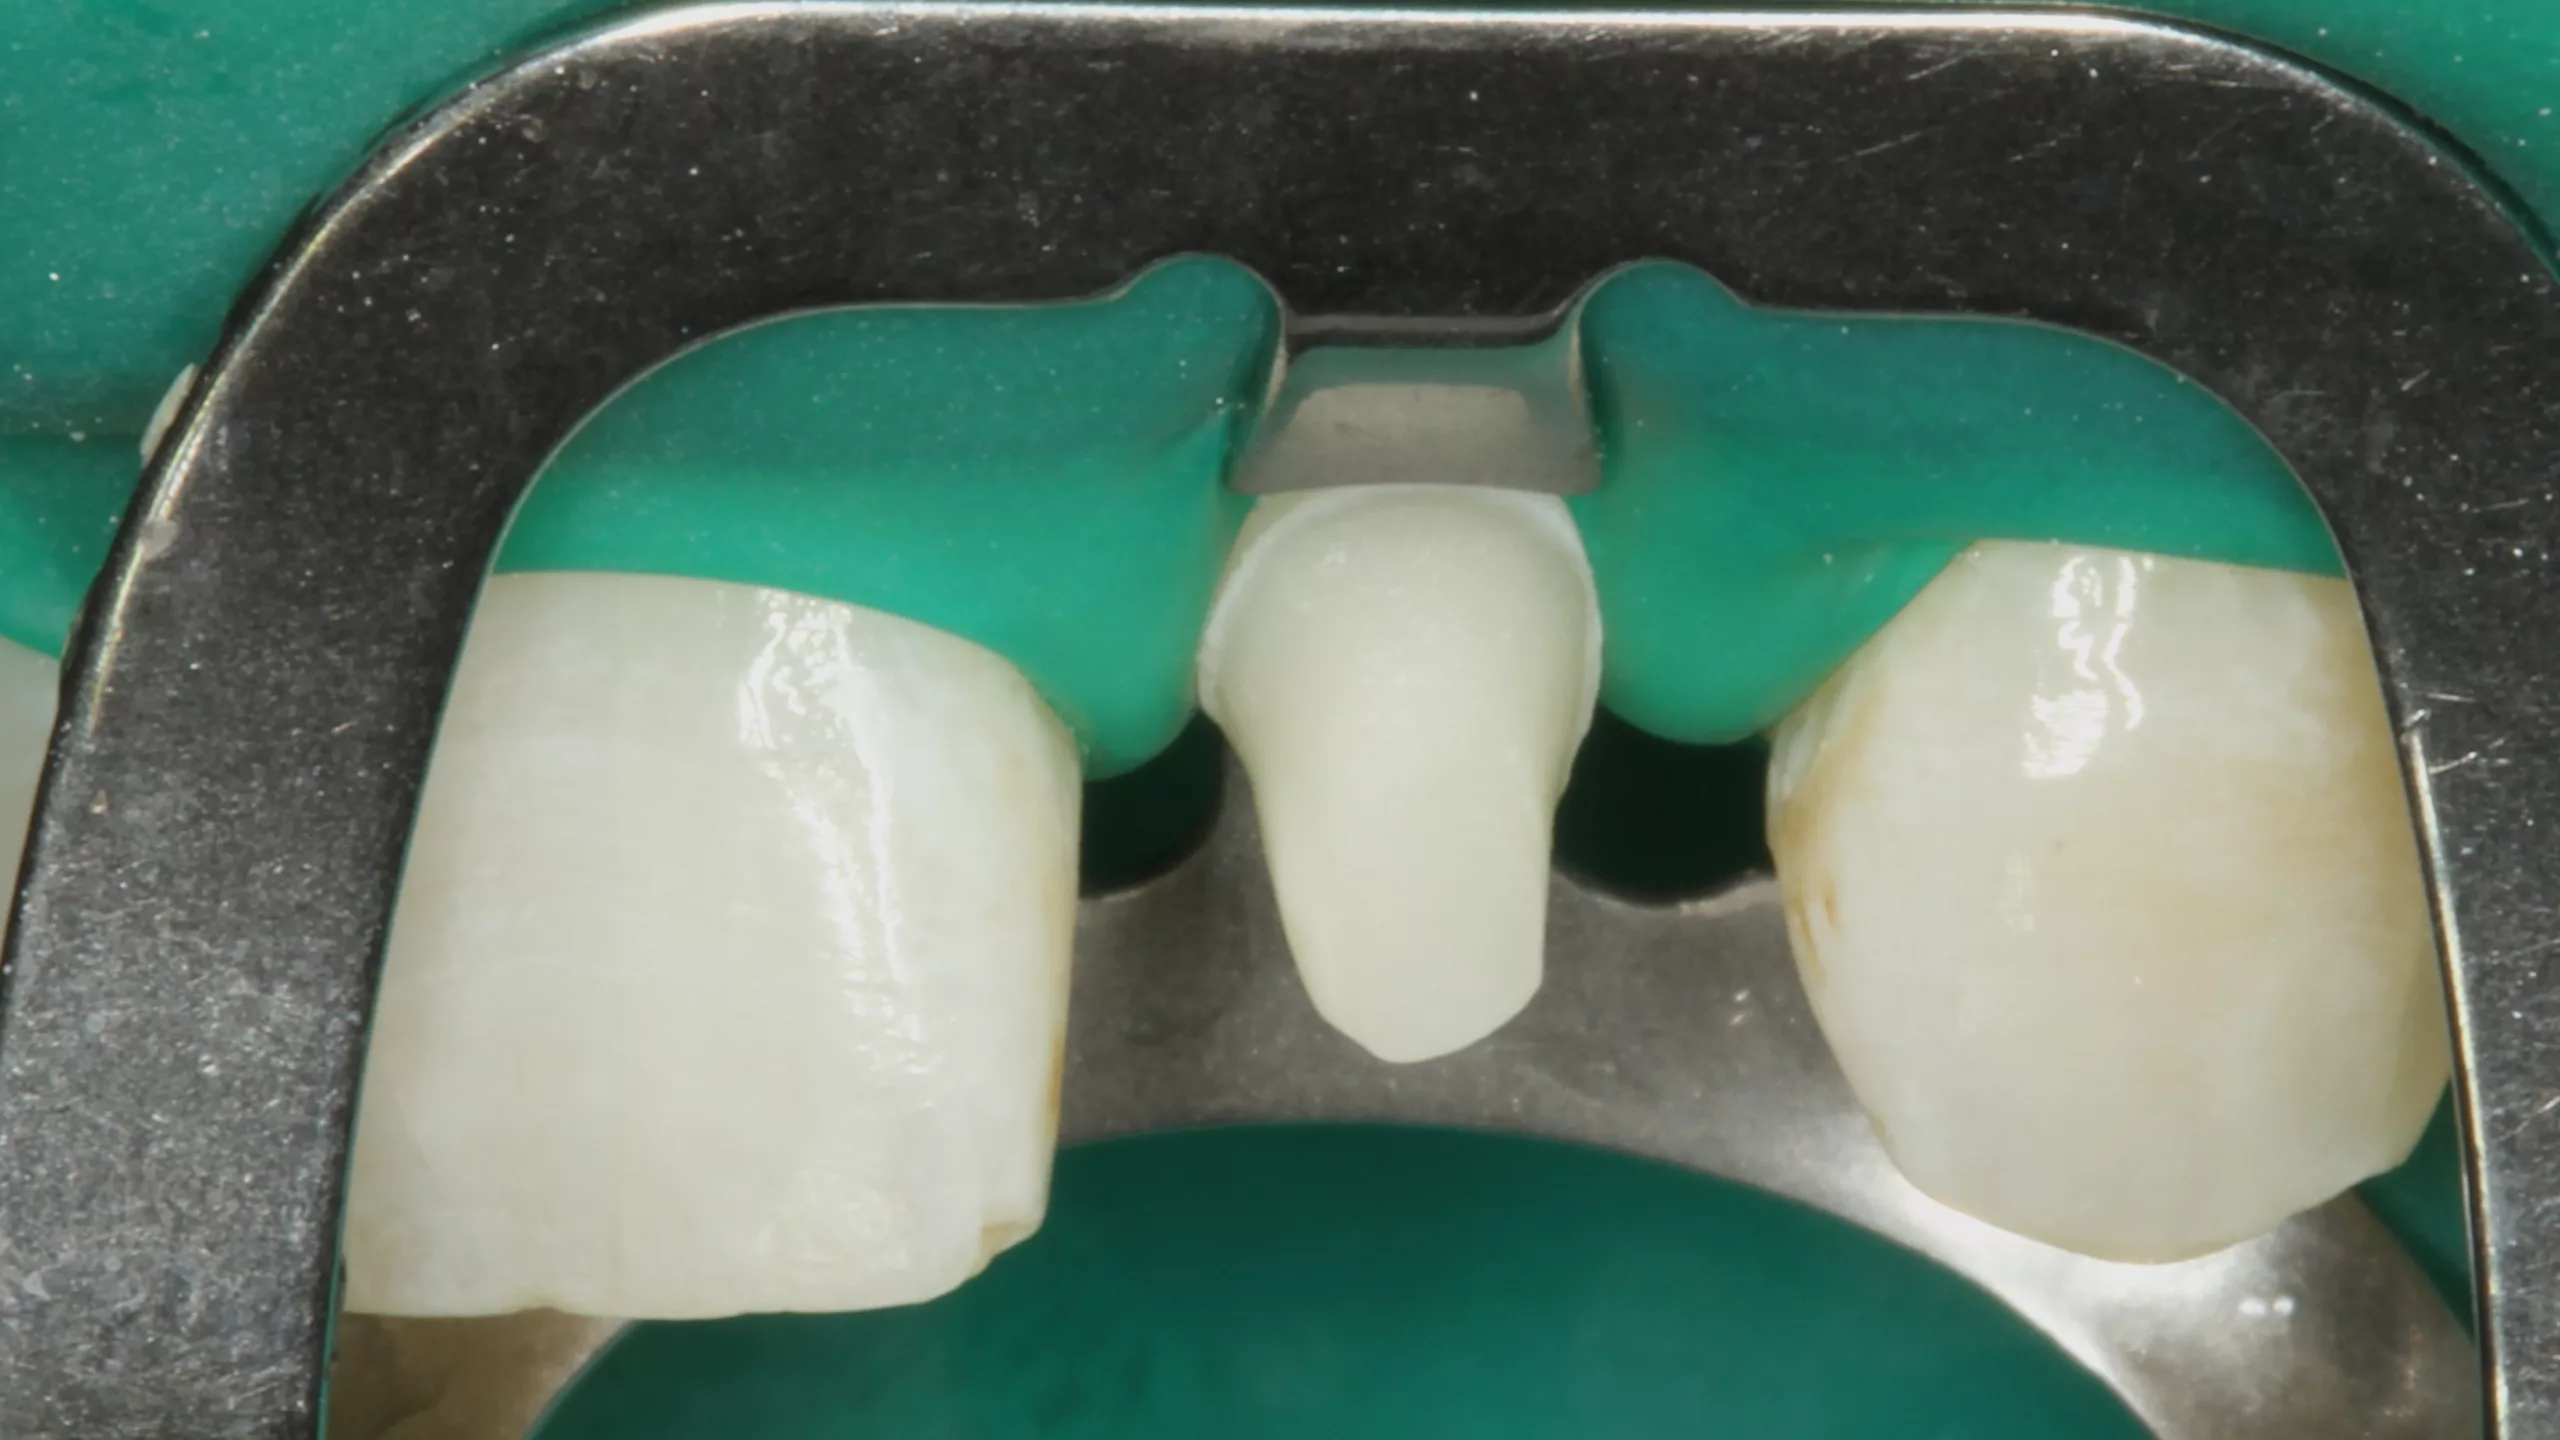

Weiter geht es am Zahn: Die Kontaminationskontrolle ist bei der adhäsiven Befestigung essenziell [84]. Das einfachste Tool – gerade bei adhäsiven Teilkronen – ist die Kofferdamisolierung. Die Abbildung 2 zeigt den isolierten Arbeitsbereich nach Entfernung der Provisorien, der Reinigung der Klebeflächen mit Ultraschall und Bims-Paste (Zircate, Dentsply Sirona) sowie dem Abstrahlen der Kompositfläche an Zahn 46 mit 50 ?m Aluminiumoxid (Rondoflex, KaVo). Die kurze, flügellose Molaren-Kofferdamklammer erleichtert den Zugang zum Approximalraum bei der Versäuberung mit Zahnseide. Da es sich in diesem Bereich um eine adhäsive Kavitätenbodenelevation mit Komposit [66] im Vorfeld der Präparaton und nicht um eine adhäsive Aufbaufüllung handelt, kommt der suffizienten Vorbehandlung auch dieser Klebefläche eine entscheidende Bedeutung zu, um einen Haftverbund zwischen dem Komposit und dem adhäsiven Befestigungssystem zu gewährleisten.

Nach der Schmelzkonditionierung mit dem Phosphorsäuregel und dem ausreichenden Spülen für 15 Sek. ist für eine suffiziente volladhäsive Anbindung ein Benetzungsmittel, ein „Tooth Primer“ erforderlich. Der zu Visalys CemCore gehörende Visalys Tooth Primer ist ein selbstkonditionierender Einkomponenten-Primer, der keiner separaten Lichthärtung bedarf und somit die Ansprüche an die Selbsthärtung des Adhäsivs, die anschließend im Kontakt mit Visalys CemCore abläuft, erfüllt. Die Abbildung 3 zeigt die Einwirkung des Visalys Tooth Primers auf die Präparationsflächen der beiden Zähne 46 und 47. Die Befestigung der Teilkronen erfolgte gleichzeitig mit Visalys CemCore in der Farbe Universal (A2/A3), das vorab direkt auf die Teilkronen und nicht in die Kavitäten appliziert wurde (Abb. 4). Obwohl eine „Tack Cure“-Technik-Option zur Verfügung steht, wurden die Überstände des Befestigungsmaterials mittels Modellierspatel, frischem Bondingpinsel und Zahnseide entfernt. Die im Vergleich zu herkömmlichen Befestigungskompositen etwas höhere Konsistenz und bessere Standfestigkeit (kommt primär der Funktion als Stumpfaufbaukomposit zugute) erleichtert die Überschussentfernung immens, da das Material nicht so schnell unkontrolliert wegfließt. Es erfolgte eine initiale Härtung mittels eines Hochleistungs-LED-Polymerisationsgerätes. Zur Verhinderung der Sauerstoffinhibitionsschicht kann jedes herkömmliche Glyceringel verwendet werden. Alternativ kann die ebenfalls von Kettenbach angebotene Visalys CemCore Try In-Paste zur Anwendung kommen. Obwohl Visalys CemCore eine ausgezeichnete Selbsthärtung aufweist, erfolgte dennoch eine Lichthärtung unter Glyceringel für 20 Sek. pro Fläche. Die Überprüfung der statischen und dynamischen Okklusion darf erst nach Abschluss der Dunkelhärtung vorgenommen werden, damit die adhäsive Integration nicht gestört wird, wenn im Polymerisationsprozess durch Exkursionsbewegungen mechanisch auf die Klebefläche eingewirkt wird.